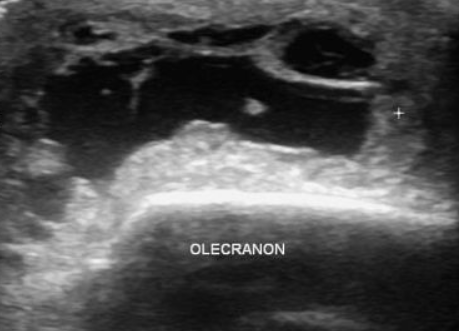

초음파상 주두 표층으로 검은색의 저에코로 보이는 점액낭염